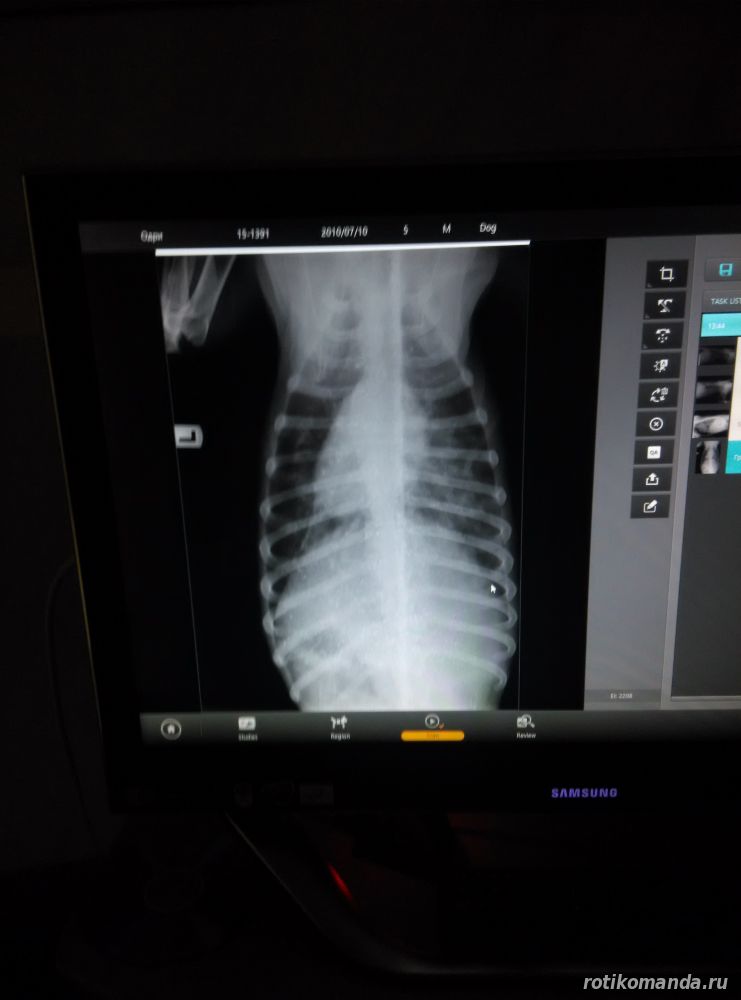

| Сегодня была у Одри два раза. Привезла ей вареную индейку, чему она была очень рада. Кушает с жадностью. Разговаривала с врачом. По результатам узи и рентгена ситуация такая: изменения пояснично-крестцового угла, надо делать МРТ, но сейчас в ее состоянии это невозможно. Также рефлексы снижены, глубокая болевая чувствительность отсутствует, атония мочевого пузыря, ушиб легких, пневмоторакс (( Все это результат травмы. То, что ее сбила машина, конечно можно предположить, но врачи говорят, что тогда бы были повреждения на шкуре или гематомы. Как это ни печально, но все склоняются к тому что это сделали нелюди ((( Фото будут чуть позже.